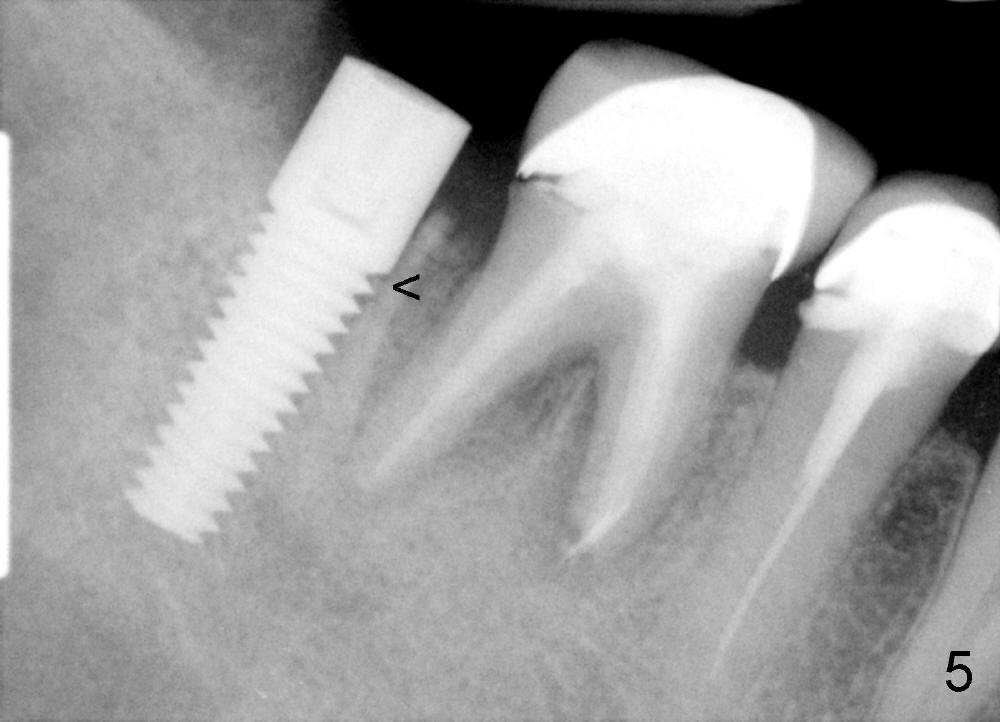

A 5x17 mm implant is placed (Fig.3).  When the gauze is removed, copious hemorrhage resumes, which is stopped by pressing into the defect with mixture of autogenous bone (harvested from osteotomy in the mesial socket of the 2nd molar) and 3.5 g of allograft (Fig.4: B).

Three and a half months postop, the density of the previous cyst area increases apparently, while the bone grows into the threads of the implant (Fig.5 <, as compared to the same area of Fig.3,4).  The implant is ready for restoraton.